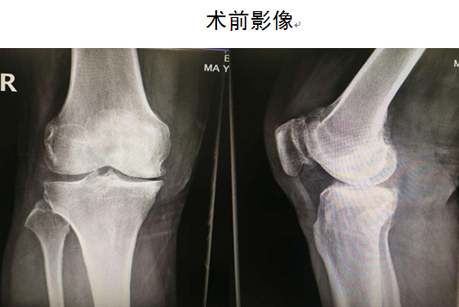

患者刘先生,右膝关节疼痛多年,伴行走困难,逐渐加重,严重影响日常生活,曾于多家医院就诊,均建议其行全膝关节置换术。遂于近日入住我院关节外科,拟行“右侧膝关节全膝人工关节置换术”。

关节外科-创伤骨科主任马东印、副主任医师王兴龙通过详细查体及全面影像学检查,综合评估病情后,考虑患者为单纯右膝关节内侧间室骨性关节炎,外侧间室关节软骨尚完好,且十字韧带及内外侧副韧带也均完好。患者年龄刚六十有余,若行全膝关节表面置换为时尚早,更为可惜的是,手术需切除患者完好的外侧间室软骨及正常的十字韧带,虽能缓解疼痛,但关节功能会受很大影响,患者将不能进行深蹲、快走等灵活性活动。经过和患者充分沟通,决定为其行“右膝内侧单髁关节置换术”。经过仔细制定个体化手术及术后康复方案后,成功为患者实施了右膝关节单髁置换手术。术后第二天患者即下床活动,第五天即行走自如,彻底解决了患者疼痛及关节功能问题。